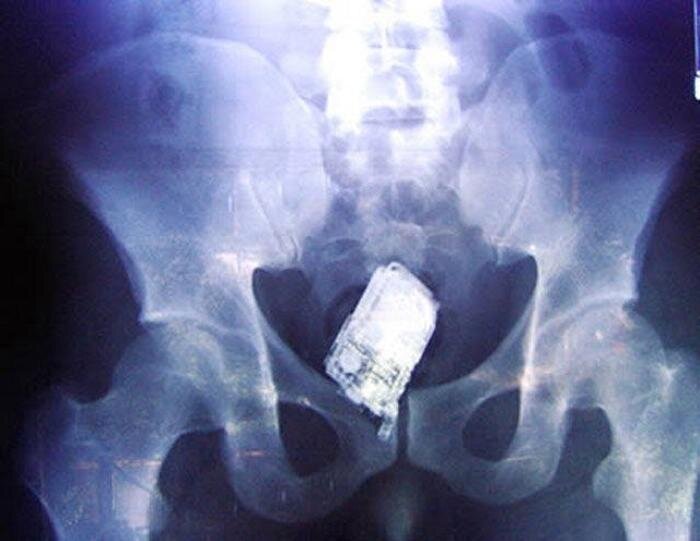

Мобильный телефон в анальном отверстии